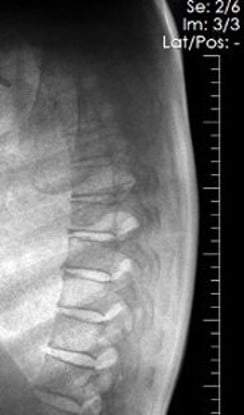

This 67-year old female patient presented to the ER with shortness of breath, in conjunction with chronic pain in her posterior thoracic region upon taking a large breath in. The reading radiologist noticed a suspicious mass-like opacity in the Lateral view. The radiologist stated that, thanks to the DE images, they could they tell the opacity wasn’t a lung mass, but instead far less concerning bony outcroppings from the thoracic vertebrae.